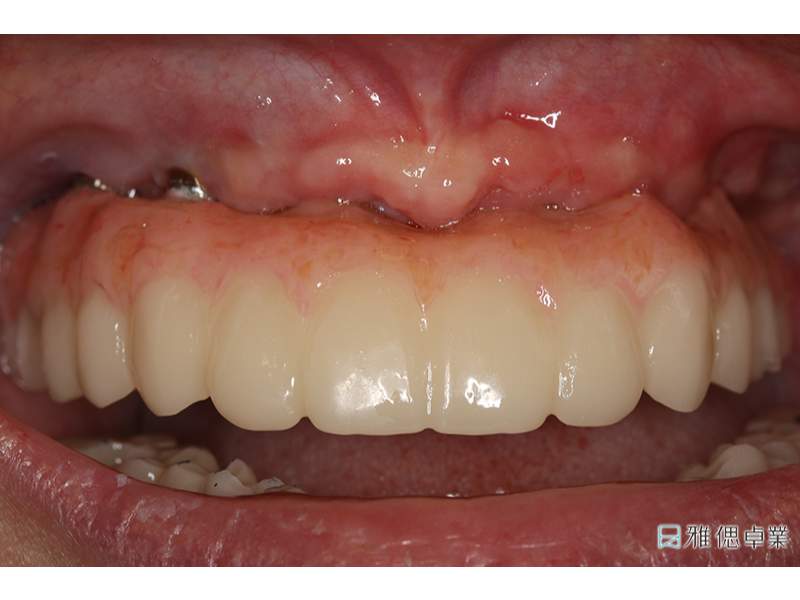

All on 6正式假牙(上顎)

術後